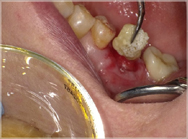

上記の写真はリッジプリザベーションにPRGFを用いたもので、非常に高い効果を得ることができます。

●通常の治療

抜歯直後

抜歯してできた穴にPRGFを入れると、上皮や骨の再生が促進され、短期間で抜歯窩がふさがります。また、抜歯後の痛みと腫れも軽減します。

一方、自然治癒を待つ場合には、穴が完全にふさがるまでに数ヶ月かかります。その間にドライソケット(抜歯窩治療不全)になったり、食べ物が詰まるなど、痛みや悪臭を伴うこともあります。